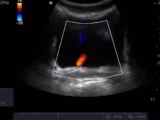

Measurement of systolic blood pressure using POCUS with color Doppler compared to with an intraarterial line

Henry Mayo-Malasky; Daniel Ying; Alekhya Bukkuri; Paul H. Mayo - This study compares the measurement of SBP using point of care ultrasound (POCUS) with color Doppler to the measurement of SBP using an intraarterial catheter